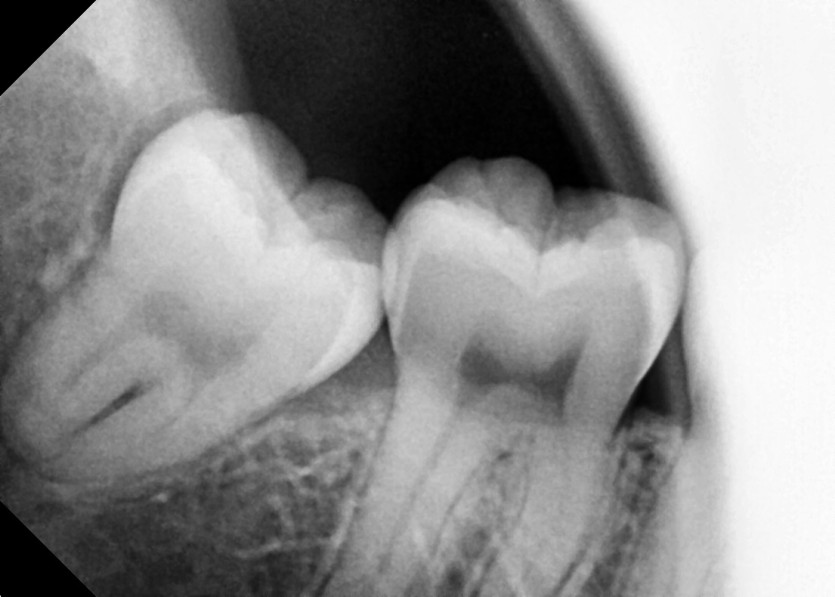

#48 사랑니 발치

구강 외과 전문의가 당일 발치했습니다.